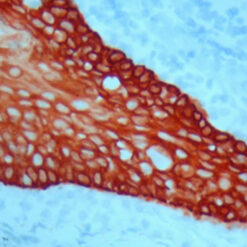

Lambda Light Chain-FITC

Traces of contaminating antibodies have been removed by solid phase absorption. Only the lambda precipitation line appeared in cross immunoelectrophoresis. This antibody is well suited for tissue section staining but may also be used for other applications.

| Immunogen | Pool of human Lambda light chain isolated from the urine of patients with Bence Jones Proteinuria. |

| Description/Type | FITC Conjugated Antibody |